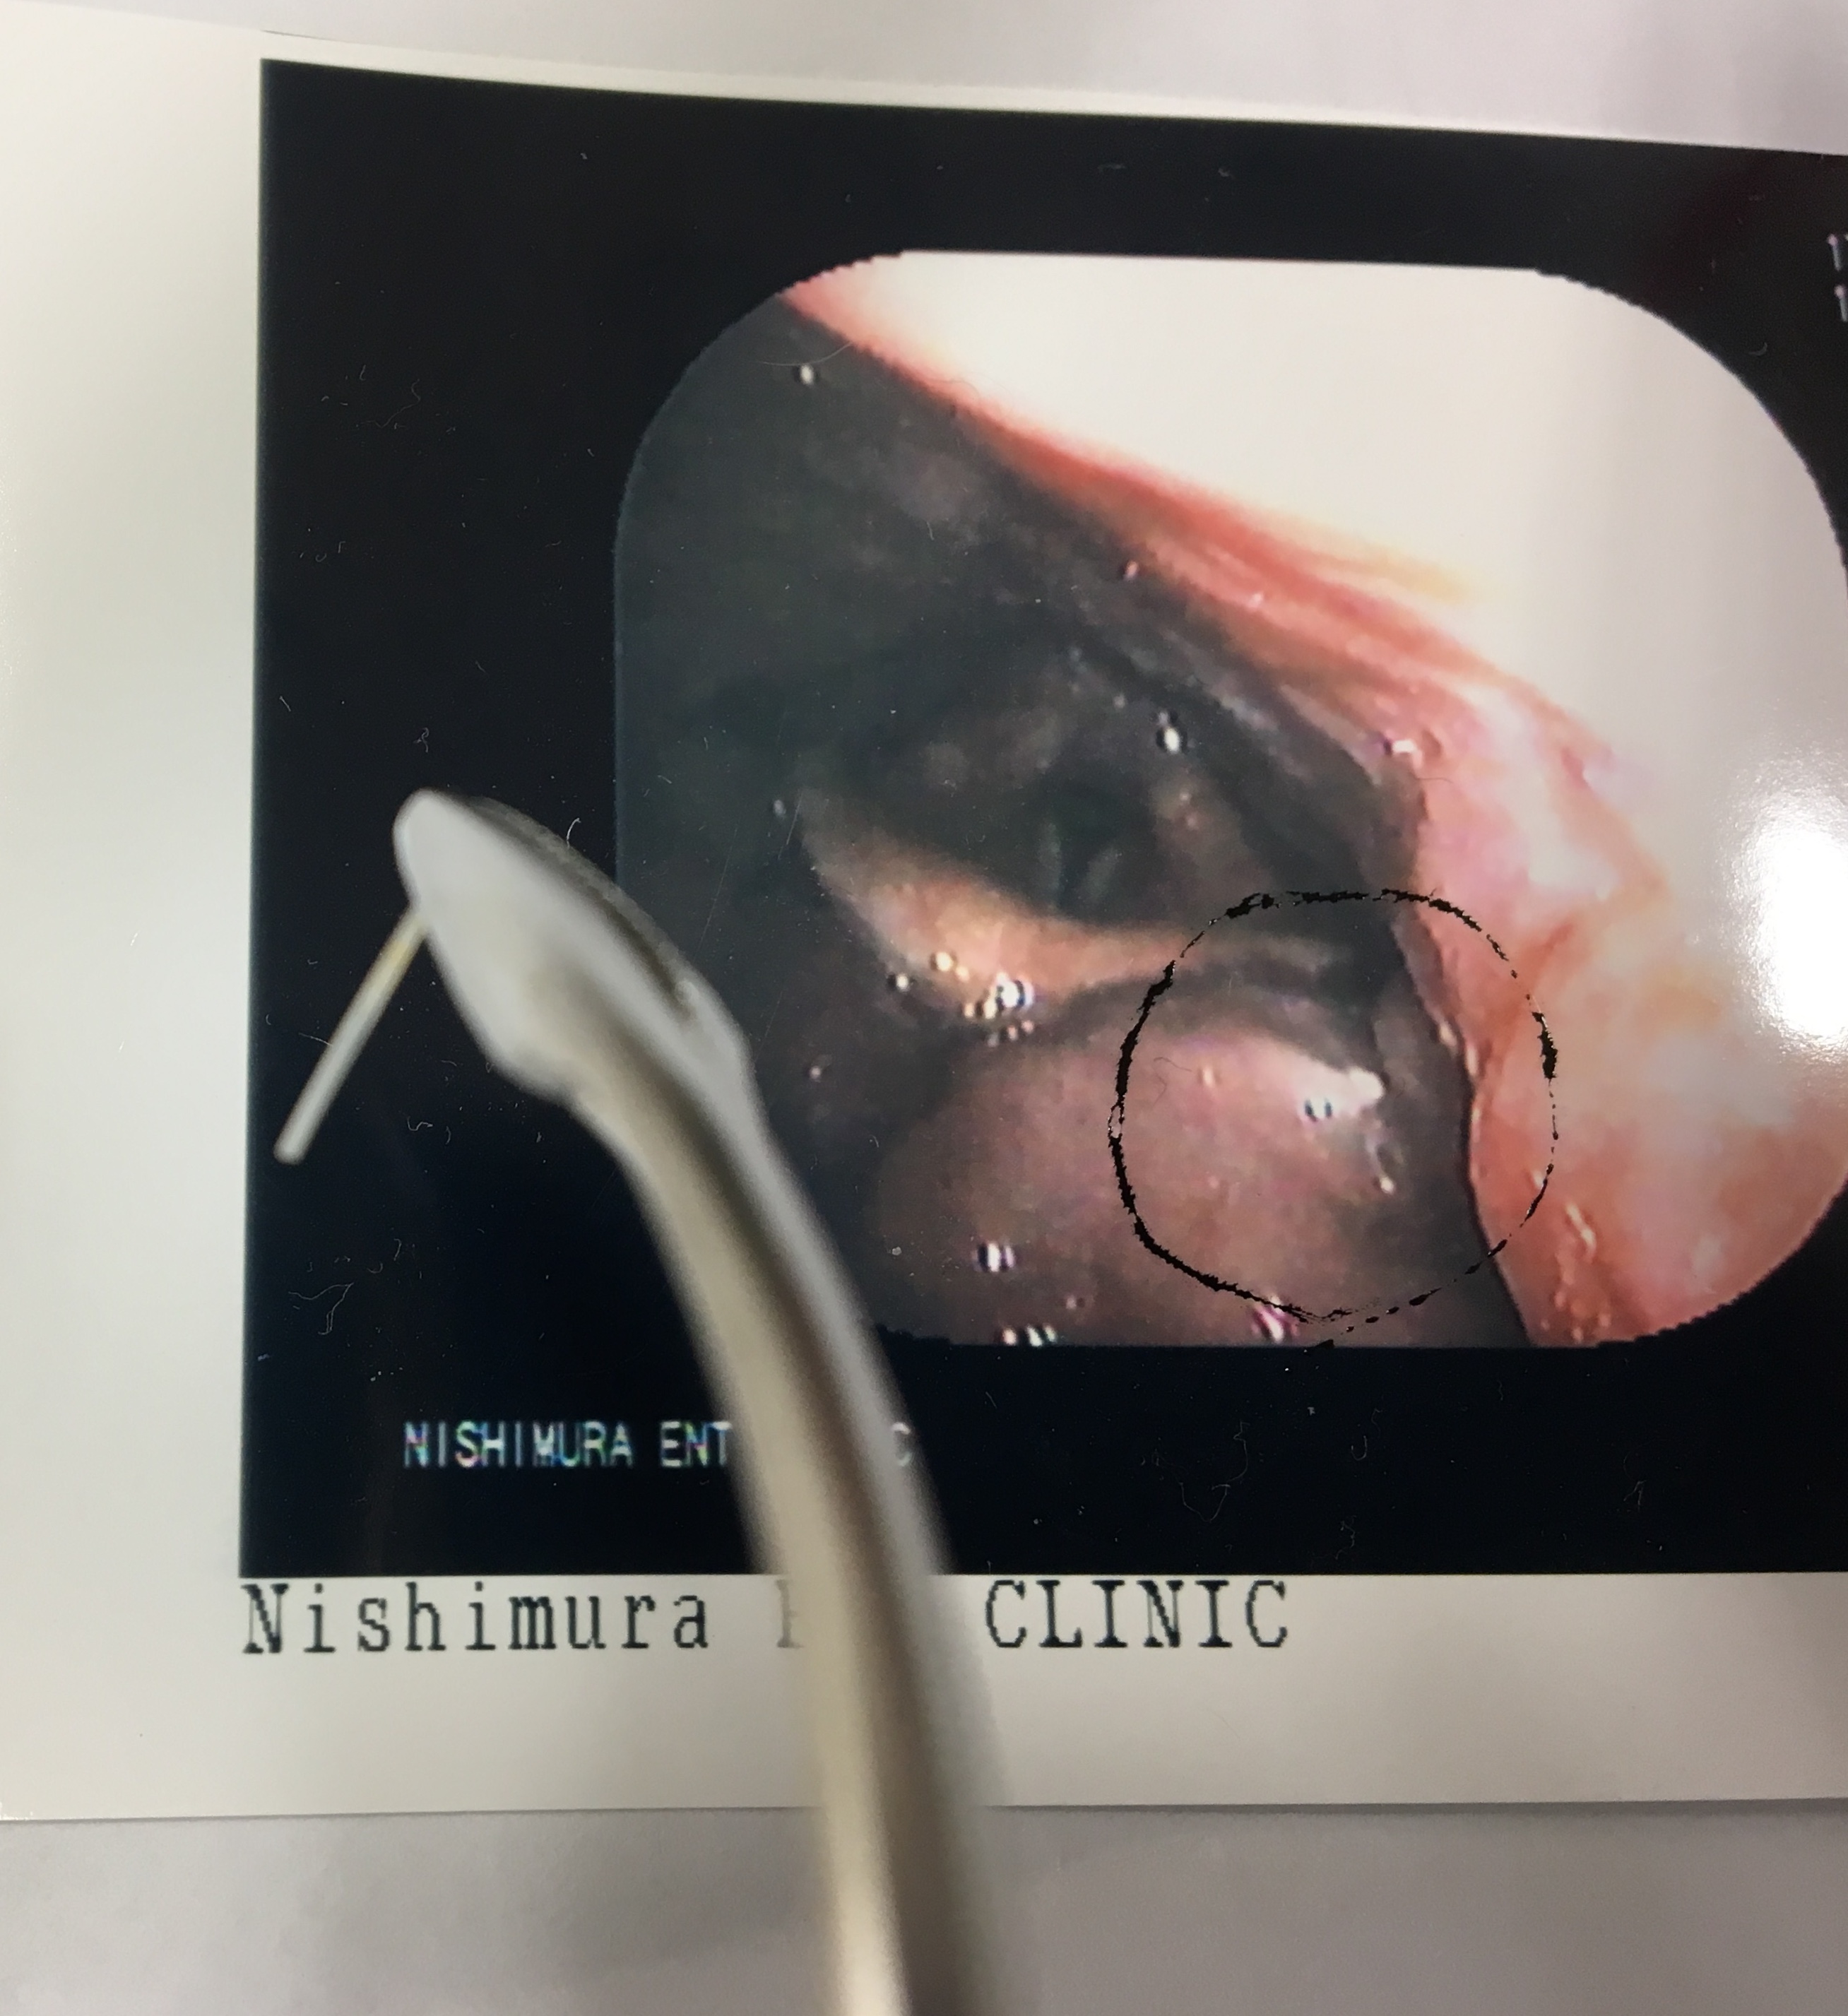

今日は自画自賛、猫が獲物を見せに来たようなお話です。

これ、舌根部に刺さったカレイの骨!鉗子付きファイバースコープが無いため、病院紹介しようと思った症例ですが、患者さんの協力もありまして、曲がりの鉗子で取れました❗️やったあ❗️